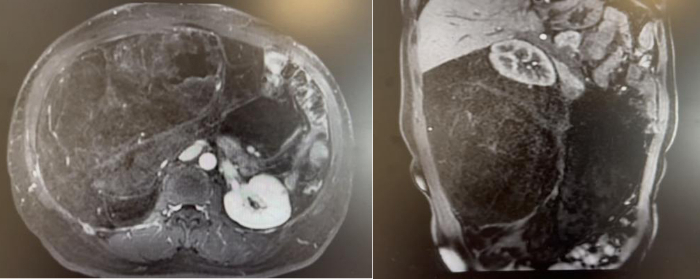

72岁男性,因体重下降2月,确诊腹膜后肉瘤10天。腹部增强CT提示左侧腹膜后巨大脂肪肉瘤,直径约30cm。

我们实施了全麻下开放腹膜后肿瘤切除术。术中发现肿瘤与结肠系膜及降结肠粘连,团队切除降结肠、部分膈肌、腹壁肌肉,横结肠和乙状结肠吻合。手术历时3个小时,出血控制在500ml以内。术后恢复良好:第2天下地活动,术后3天排气,术后1周流食,术后10天出院。